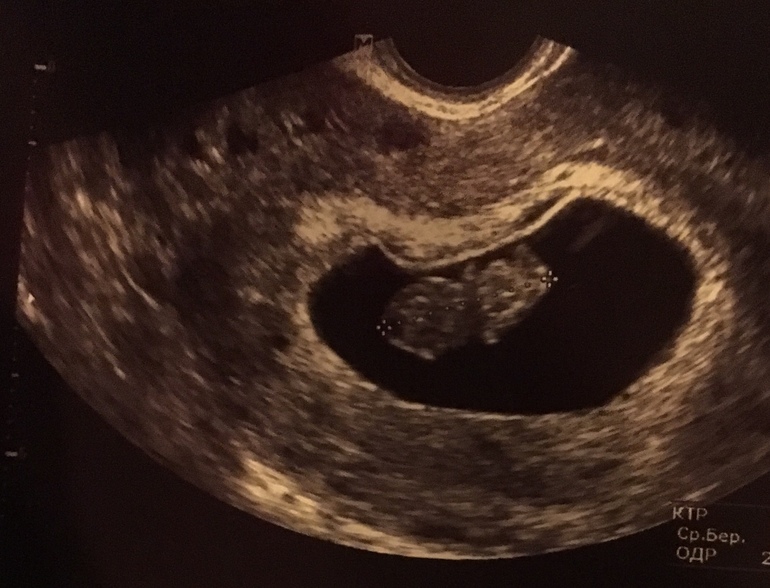

первое узи 8 неделя

узи с 8 недели